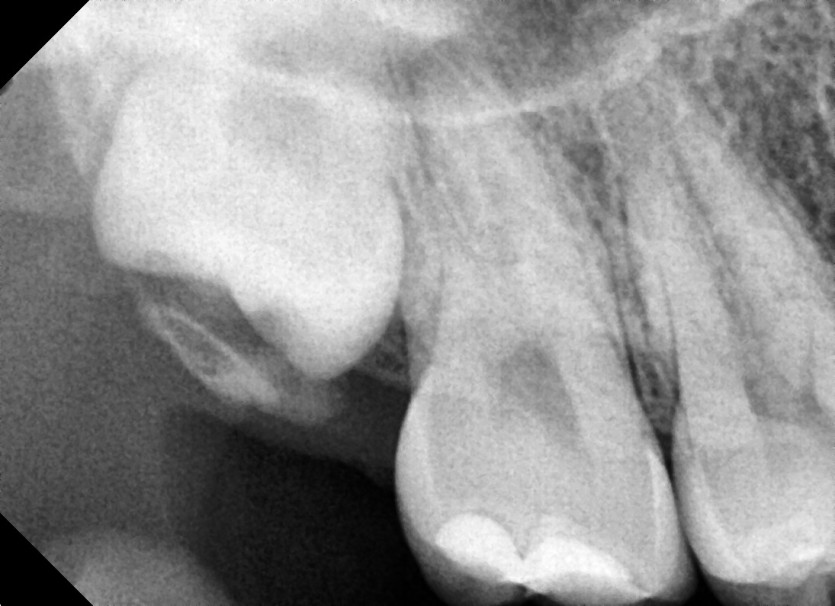

#18,48 사랑니 발치

구강 외과 전문의가 당일 발치했습니다.